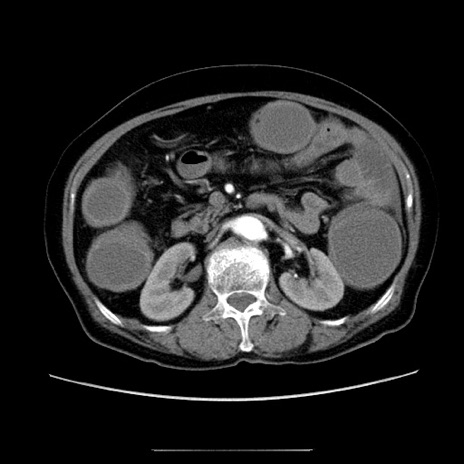

冠状断像

【症例】70歳代女性

【主訴】お腹が張る

【現病歴】1週間くらい前から腹部膨満の自覚あり。昨日夜から増悪したため、本日救急外来受診。

【身体所見】意識清明、BT 36.5℃、BP 165/106mmHg、HR 80bpm、SpO2 98%、腹部:膨満、軟、自発痛・圧痛なし、触診にて不快感あり、腸蠕動音:減弱

【データ】WBC 12600、CRP 1.04